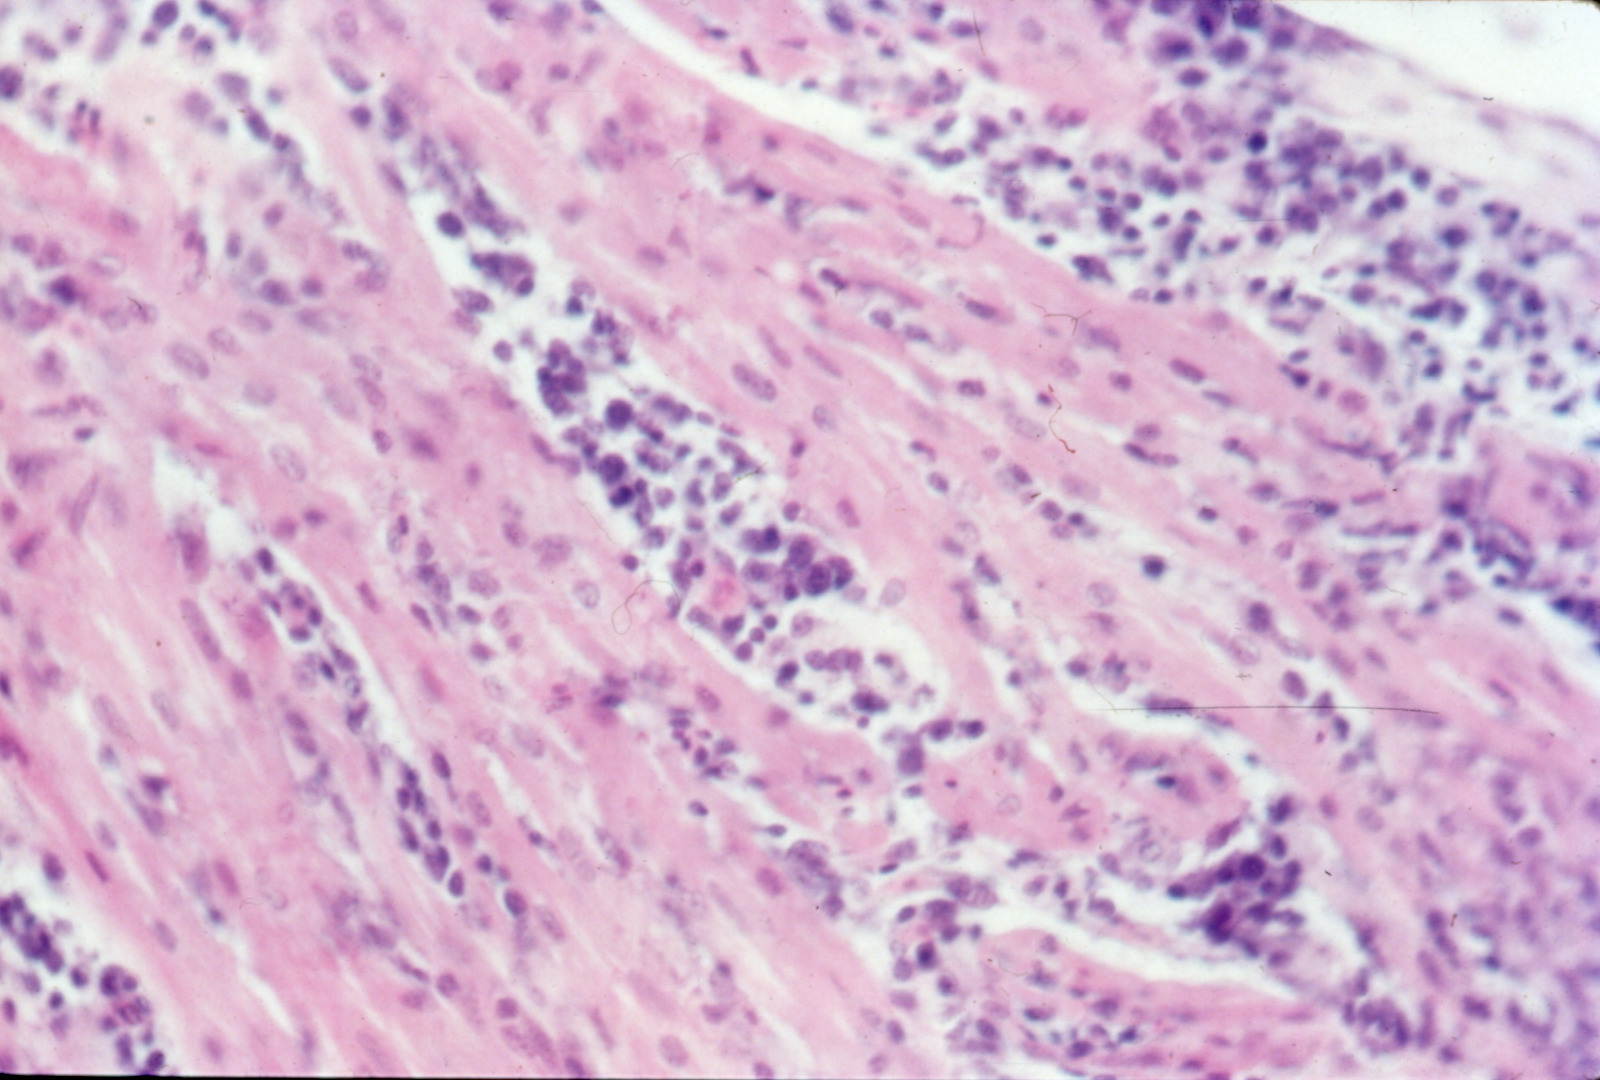

Avian encephalomyelitis (slide study set no. 5)

Avian encephalomyelitis Avian medicine Chickens--Diseases Turkeys--Diseases Pheasants--Diseases

Slide Study Set #5, Avian Encephalomyelitis, 2 sets (includes 32 color slides), 1974